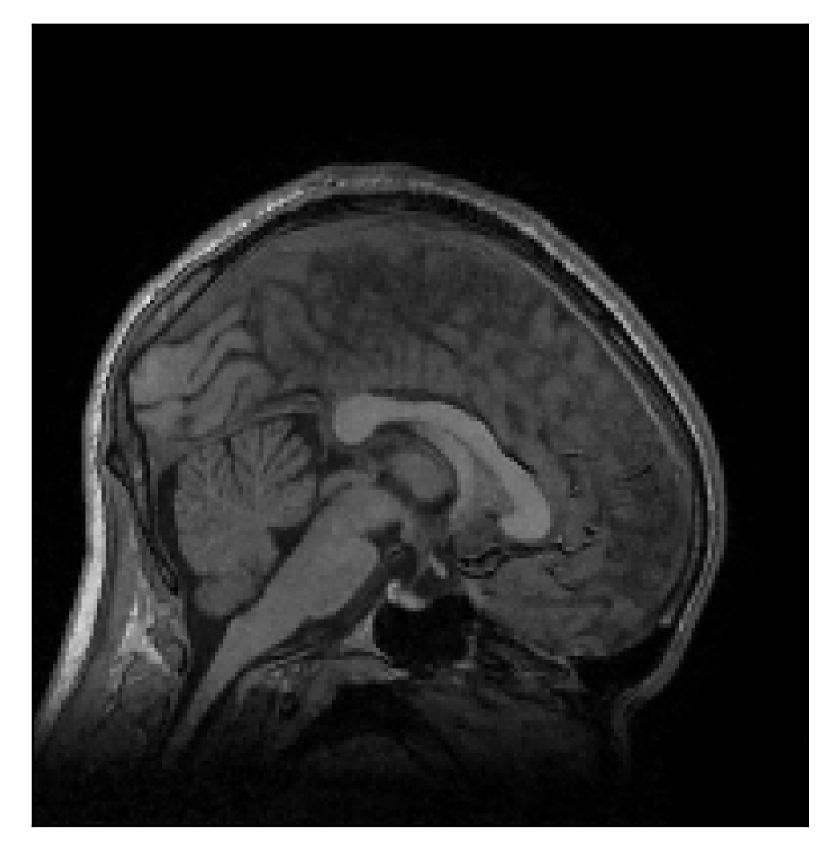

4.3 Experiment 3: scanner reconstruction vs raw k-space data

The results of the two experiments described in Section 3.3 are depicted in Figures 12 and 14. The main difference between the two experiments is related to the input data for the proposed motion-correction algorithm.

In the first experiment, the corrupted contrast has been acquired with a protocol based on a linear filling pattern in -space. Note that, in this particular case, the scanner reconstruction implements the SENSE method. We then extracted the DICOM of both amplitude and phase produced by the scanner, and used it as input data (after a Fourier transform) for the algorithm. The proposed scheme is able to successfully remove the motion artifacts in Figure 12.

In the case of randomized sampling, the scanner reconstruction is not adequate as input data for the proposed motion-correction algorithm, because it employs a compressed-sensing algorithm. We speculate that compressed-sensing reconstructions degrade the information contained in the corrupted volume, and the corrected contrast cannot be effectively recovered by simply removing rigid-motion artifacts (we defer the degraded results when using scanner reconstruction data in Appendix A). However, when the input data is obtained by directly processing the raw -space data via the SENSE reconstruction, the motion-correction scheme is able to successfully remove the motion artifacts (Figure 14).

The motion-corrected full-volume scans were analyzed by a neuroradiologist with 16 years of experience. These were generally deemed of good radiological quality. The motion-related artifacts have been completely removed, and the results are quite close to the ground truth. In Table 3, we organized a more detailed qualitative analysis of the 3D results, geared toward a radiological assessment of the corrected scans.

| Section 3.3, Figure 12 | T2 | Completely corrected | No blurring | No additional artifacts | |

| Section 3.3, Figure 14 | T2-FLAIR | Completely corrected | Some blurring | No additional artifacts | Good grey white matter differentiation |